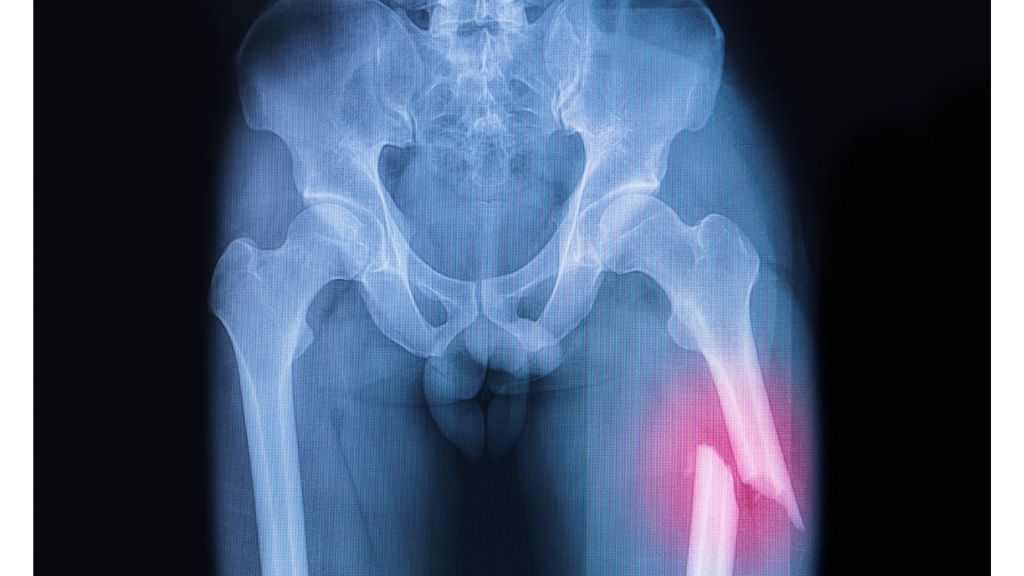

Fat globules may be introduced into the blood vessel from the fat spaces in bones when there is a fracture. Fat embolism may be seen in 5-10% of patients with pelvic or multiple long bone fracture. Other causes of fat emboli include surgical procedures such as liposuction and acute pancreatitis.